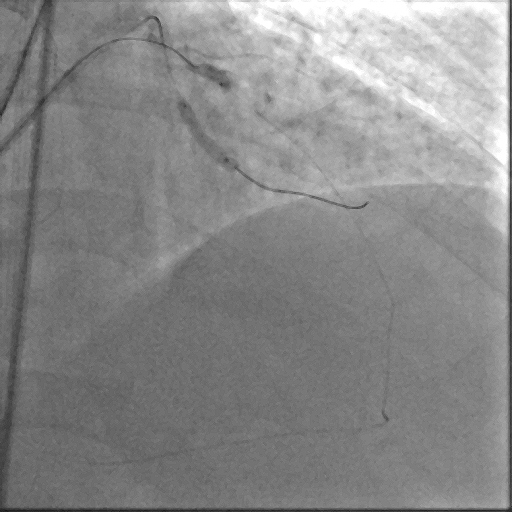

Coronary angiography demonstrated a right-dominant system with significant ostial LCx stenosis and a blunt ostial LAD chronic total occlusion, with a J-CTO score of 4. The RCA showed mild coronary disease and supplied collateral flow to the LAD territory, graded as Werner CC2.

Through bilateral femoral access, 7Fr EBU 3.5 and JR 4.0 catheters were engaged to the left main and RCA. With no antegrade entry, a retrograde marker wire and IVUS-guided antegrade puncture using Gaia Next 2 and Conquest Pro with Finecross failed, as both wires were deflected by the calcified cap despite tip modification with a secondary curve. A retrograde attempt using Gaia Next 2 and 3 with Finecross also failed.Suspecting LAD angulation, an antegrade re-attempt was performed using IVUS-guided puncture with a Conquest Pro 8-20 supported by a Supercross90 under retrograde wire guidance, successfully puncturing the proximal cap. Supercross was exchanged for Finecross, and the wire crossed distally, but Finecross and Corsair Pro XS could not advance due to the tight lesion. After proximal preparation and the anchor balloon technique in the LCx, the microcatheter advanced distally and the wire was exchanged for a workhorse wire. Retrograde injections confirmed true lumen position, and the LAD was predilated. IVUS showed mixed plaque and myocardial bridging in the mid LAD and mixed plaque at the ostial LCx. Further preparation was performed with a 3.5 mm scoring balloon. A hybrid strategy using a 4.0¡¿20 mm DCB for the LCx and a 4.0¡¿32 mm DES from LM to LAD, followed by 5.0 and 4.0 NC balloons for post-dilatation, achieved final TIMI 3 flow without complications.

This case demonstrates a complex left main bifurcation with a blunt ostial LAD CTO and tight ostial LCx stenosis, successfully managed through a hybrid strategy. When both antegrade and retrograde approaches failed, IVUS-guided puncture with a Supercross-supported high–tip-load wire enabled successful revascularization. The angulated microcatheter preserved the wire¡¯s penetration force, allowing puncture of the proximal cap. Procedural safety was enhanced by a retrograde marker and tip injection confirming distal cap position, while intravascular imaging provided the precision required for safe execution and optimal procedural outcomes.